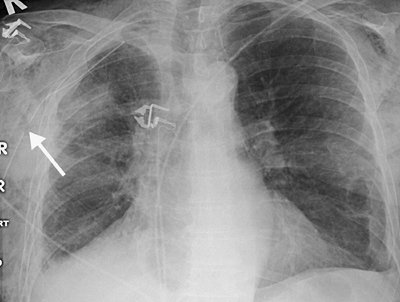

FIGURE 5-8. Hemothorax as a complication of central venous catheter placement. A: PA chest radiograph shows a normally positioned right jugular central venous catheter. B: PA chest radiograph after removal of the right catheter and placement of left subclavian central venous catheter shows a new large left pleural effusion. A chest tube was placed, which drained bright red blood.